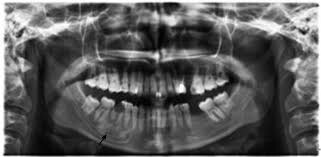

It's slightly peculiar, but since condensing osteitis symptoms are often not present, most diagnoses aren't made until you see your dentist. It's there during a regular dental checkup while receiving a routine X-ray, the pulp of your tooth is examined. The bone growth looks opaque under your root within the X-ray — whereas bone destruction would appear transparent, accompanied by pain and discomfort. Condensing osteitis is relatively uncommon. It consists of only 2% of conditions diagnosed during a routine X-ray exam, according to a study published in Dentomaxillofacial Radiology. The use of diagnostic x-ray equipment allows your dental professional to assess the bony area without a biopsy properly. All this makes it all the more important to maintain your regular dental exams and X-rays so your dentist and dental hygienist can identify any potential issues.